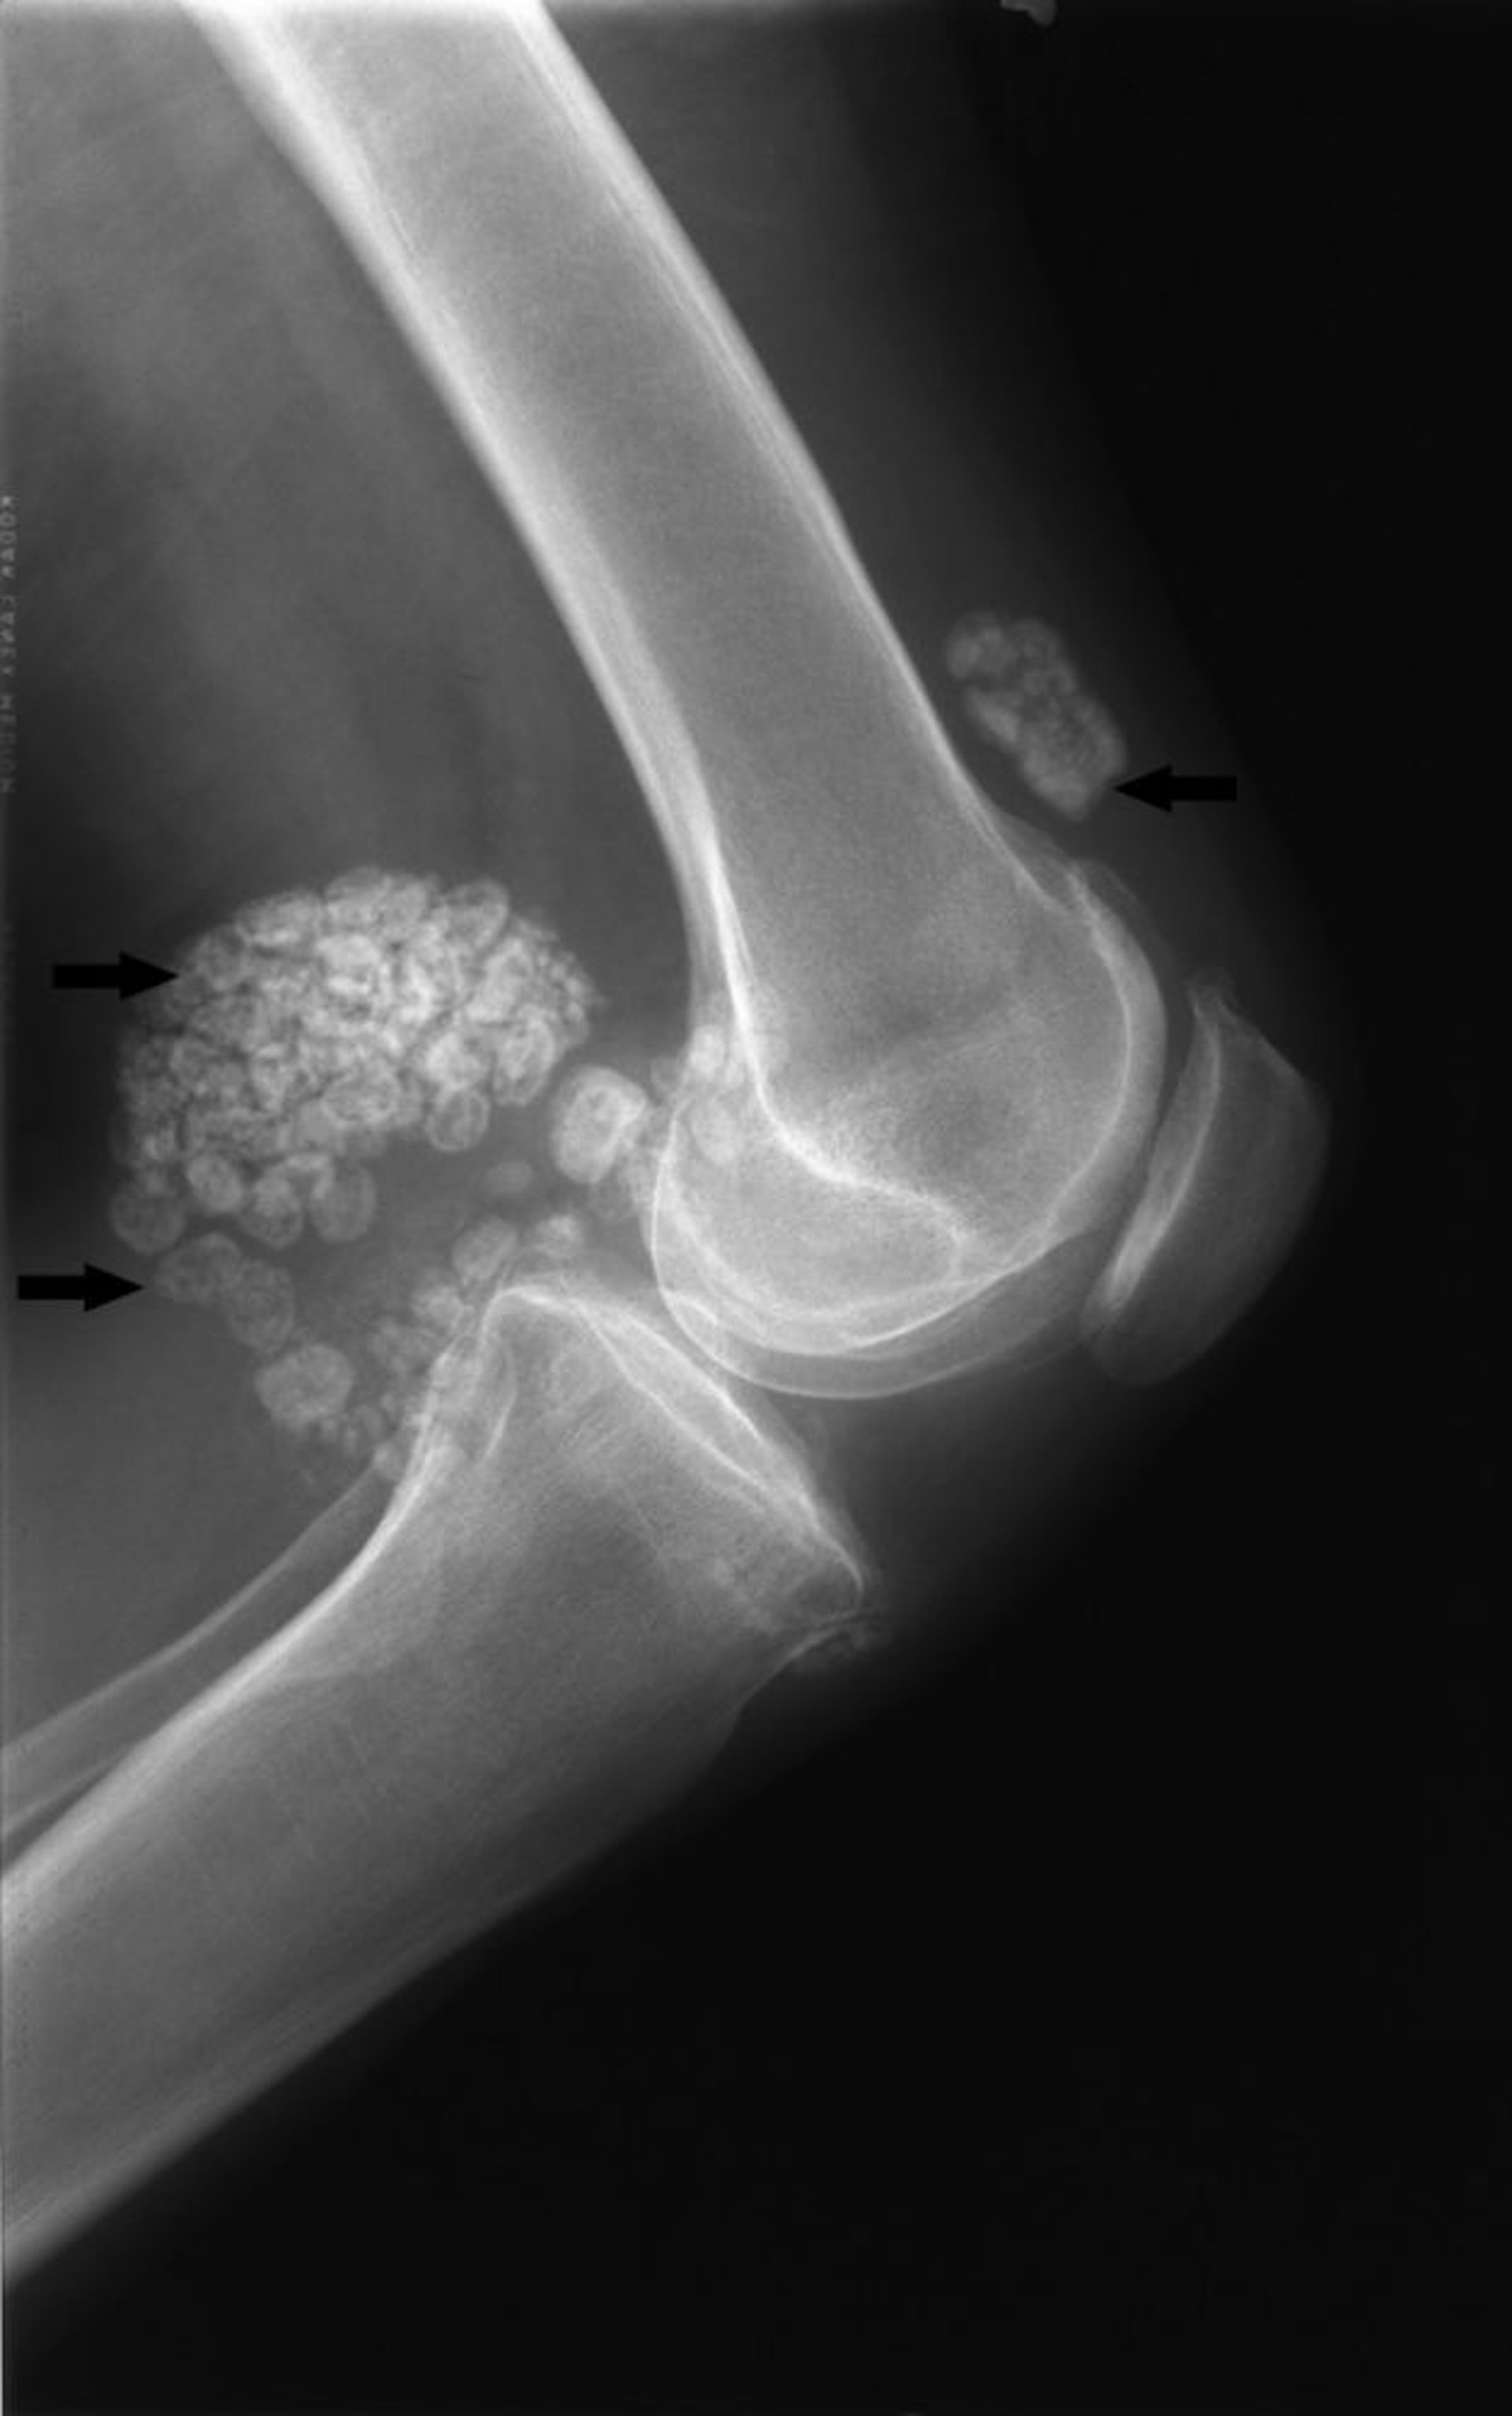

Diese Röntgenaufnahme des Knies zeigt multiple große verkalkte Gelenkkörper sowohl vor als auch hinter dem Gelenk (Pfeile), was typisch für eine synoviale Chondromatose ist.

Image courtesy of Michael J. Joyce, MD, and Hakan Ilaslan, MD.